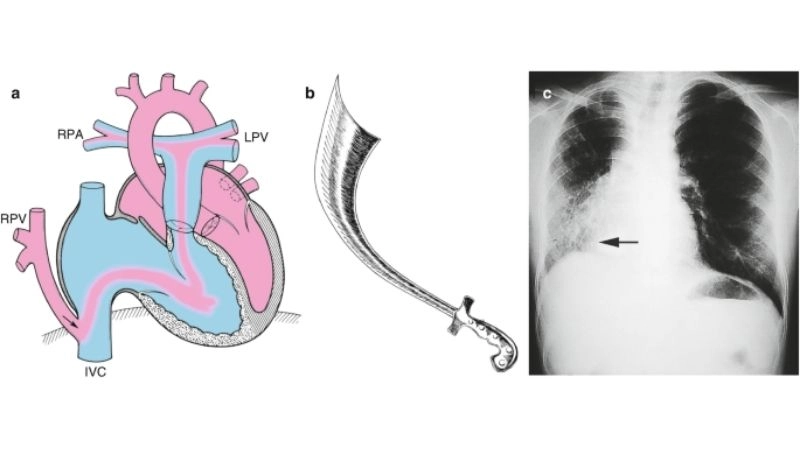

Images visual examples of partial anomalous pulmonary venous return (PAPVR)

Partial anomalous pulmonary venous return (PAPVR) is a rare congenital heart defect in which one or more pulmonary veins drain into the right atrium instead of the left atrium.